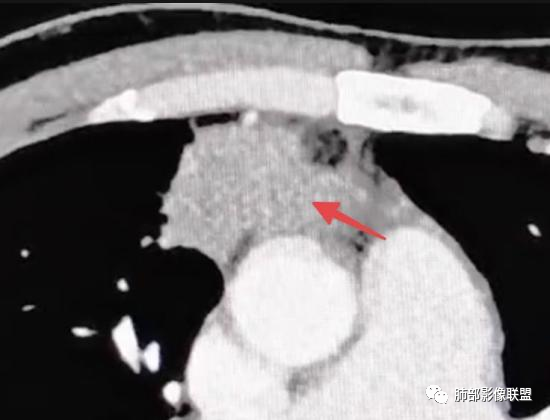

1

红箭-支气管分叉间条形高密度

2

这个脂肪间隙很模糊。

3

这里也是。还有血管增粗。

4

增大淋巴结

很多增大的淋巴结,强化方式一致均匀,

未见明确坏死,融合不明显,没有明确的分布优势。

5

这里是软组织密度,纵隔内突入

我觉得这里可以怀疑是栽桩。

肝脏病变明确,是轻度强化,延迟强化特点,边缘模糊,有轻微的包膜挛缩。